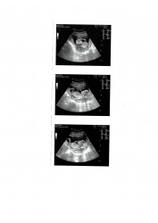

V tehotenství (stejně jako v životě) je to pořád nějaká změna. 2.6. zjistila dr. Slámová v Pronatalu, že se jedno embryo rozdělilo, dostala jsem teda hned tři fotky, ale založili jsme je do hodně hlubokého šuplíku. Hrozí hodně vysoké riziko poškození rozděleného plodu (jednovaječných dvojčat), teď musím ležet a do 12 tt se rozhodne, co bude dál.

Po krušném rozmýšlení, zda jít do rizika nebo na redukci, rozhodla příroda za nás - jednovaječná dvojčata mají ztluštění v oblasti šíje, což může znamenat genetické poškození nebo to, že špatně pracuje srdce. 1.7.2008 bude provedena redukce ze 3 na 1. Pak ještě trochu nervíků, jestli nepotratím a od půlky července se snad začneme konečně těšit z těhotenství.

Kontrola v pořádku, jednoče hezky máchalo rukama - jako při aerobicu. Ležím a odpočívám, těším se na UTZ 7.7., až dostanu průkazku a ujistím se, že je vše v pořádku. Průkazku už mám.